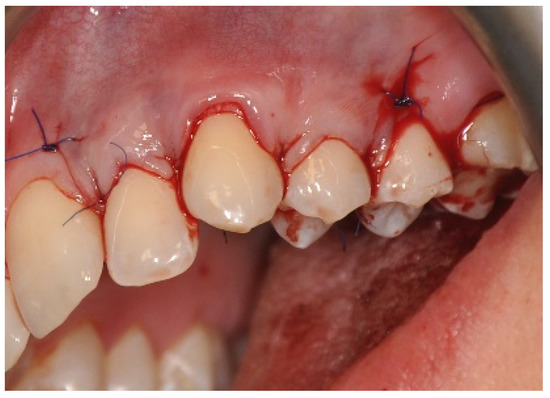

2.3. Surgical Procedures